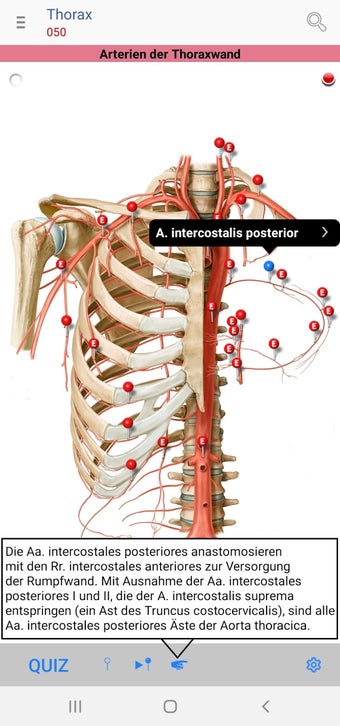

The app consists of different sections, each of which contains information about a specific part of the body. You will learn about the different organs, as well as the muscles, bones, and other important structures. You can test yourself with a unique quiz that consists of multiple-choice questions.